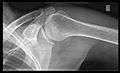

- Y-projection

The lateral contour of the shoulder should be positioned in front of the film in a way that the longitudinal axis of the scapula continues parallel to the path of the rays. This method reveals:[19]

- The horizontal centralization of the humerus head and socket.

- The osseous margins of the coraco-acromial arch and hence the supraspinatus outlet canal.

- The shape of the acromion

This projection has a low tolerance for errors and accordingly needs proper execution.[19] The Y-projection can be traced back to Wijnblath’s 1933 published cavitas-en-face projection.[20]

Y-projection conventional radiography